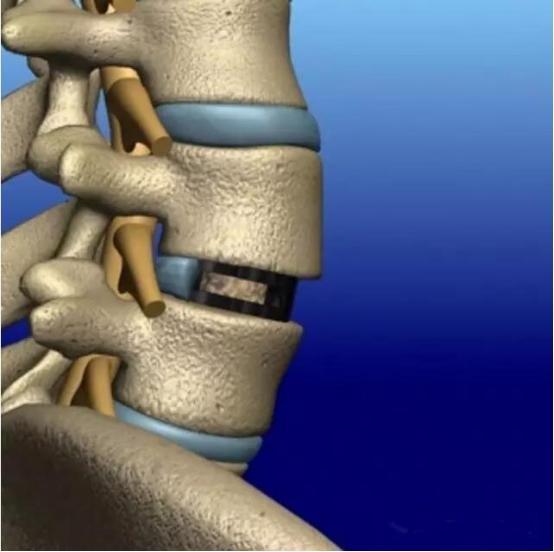

手术的大致流程就是清除导致症状的骨质增生,去除病变的椎间盘,使用各种类型的椎体融合器以及骨科内固定将两个椎体融合在一起。是不是听着很头晕,下面黑锅用大白话来解释一下!

但手术到这里并非就结束了,对于大部分病人来说,尤其是老年人,并不能保证后期就不会复发,为了减少症状复发的可能,通过骨科手术将两个椎体彻底融为一体,那可能是最有保证的。再来看这个下面这个图:

没错!那就是把中间的椎间盘也变成骨头,这样上中下全是骨头,不就相当于融合在一起了嘛!

确实如此!因此手术清除完骨赘后,就是把两个椎体中间的可能病变的椎间盘给“咬”掉,当然不是用嘴咬,而是用骨科器械清理掉。

然后为了保证椎体的高度以及椎体的稳定性,椎间盘空出来的位置要用骨头来填满,骨头哪里来的呢?前面清楚下来的骨质增生的骨头刚好可以用来填这个“窟窿”!如果骨头不够,还可以使用人工骨来帮助!

但填塞的骨头大部分都是松松垮垮的,必然会对椎体的稳定性导致影响,个子长矮了怎么办呢?因此就有人设计出了各种形态的“椎体融合器”,如下图所示:

通过在上面这些椎体融合器中填塞骨头,放置到椎间盘的位置,既能保证手术后位置的固定,而内部的骨头还能与上下椎体的骨质融合在一起。另外,近年来3D打印技术在骨科越来越得到广泛的应用,利用3D打印技术打印出来的融合器,手术后更有利于骨头的长入。

但是,又有人问了,单纯放个融合器进去占住椎间盘的位置,那么手术后也可能存在椎体的位置改变跟椎体融合器突出来呀!

确实如此!因此才需要骨科的钉棒系统来维持椎体的位置并加压固定放置的椎体融合器。